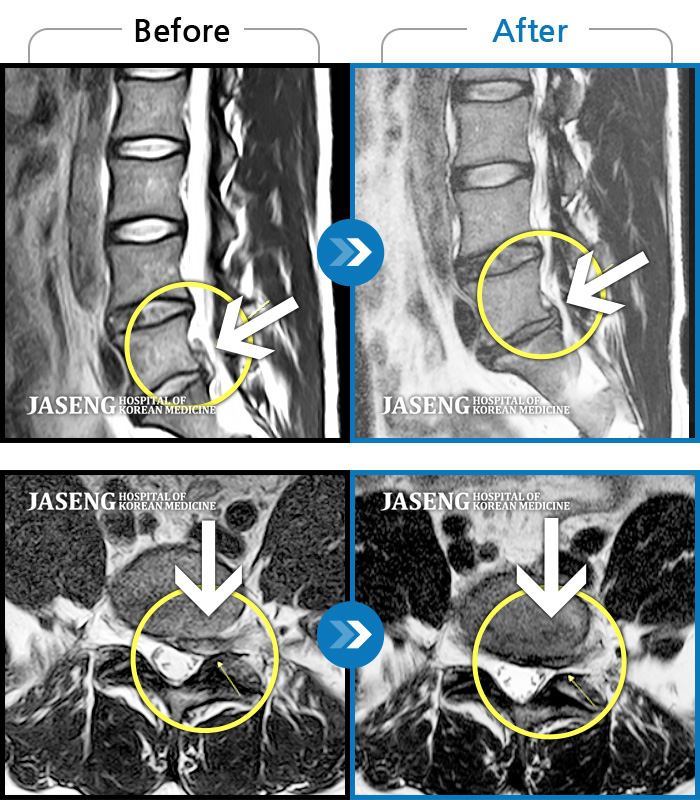

Before

After

환자에게 사전 동의를 받아 동일 조건에서 촬영되었습니다.

개인에 따라 치료 후 부작용이 발생할 수 있으니 의료진과 상담 후 치료를 진행하시기 바랍니다.

허리디스크로 내원

종아리 통증